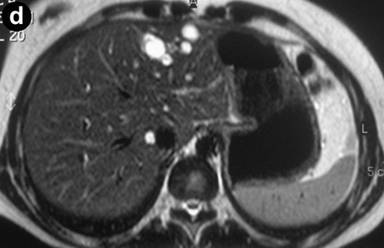

A 27-year-old female underwent a cholecystectomy for lithiasis. The patient was successively evaluated for diffuse and recurrent abdominal pain; no alcohol and/or smoking habits were reported. Laboratory measurements of total bilirubin and pancreatic amylases were unremarkable. Abdominal ultrasound was carried out which showed multiple hepatic and pancreatic cystic lesions; a dynamic enhanced CT scan confirmed the presence of multiple liver and pancreatic cystic lesions, but, in particular, the differentiation between simple hepatic cysts and cystic ectasia of the biliary ducts suggestive of Caroli’s disease was not reached. Therefore, MRI was requested to characterize the liver lesions and it was performed acquiring T1- and T2-weighted sequences integrated with T2-hydrographic images to specifically evaluate the biliary tract in axial and coronal views. MR cholangiography after intravenous administration of mangafodipir trisodium (Teslascan®, Nycomed, Amersham, Oslo, Norway), was also performed using T1-weighted sequences. Turbo spin echo T2-weighted images in axial and coronal views showed multiple hyperintense focal lesions in the left lobe of the liver, typical of cystic lesions, as well as multiple pancreatic cysts of the tail and saccular ectasia of the main biliary duct (Figure 1). T2-hydrographic dedicated images confirmed these findings, but certain imaging signs for a differential diagnosis between simple hepatic cysts and biliary cysts were not identified (Figure 2). However, the enhanced mangafodipir trisodium T1-weighted MRI clearly showed that some of the liver cysts concentrated mangafodipir trisodium contrast medium, thus demonstrating that these enhanced cystic lesions were in communication with the biliary ducts providing imaging criteria consistent with a diagnosis of Caroli’s disease (Figure 3). A segmental hepatectomy specimen demonstrated dilated simil-cystic intrahepatic ducts of the IV segment corresponding to a diagnosis of Caroli’s disease.

Figure 1. Conventional turbo spin echo T2-weighted axial (a., b. and c.) and coronal (d.) MR views show multiple cystic lesions in the left liver lobe as well as in the pancreatic tail. Saccular ectasia of the main biliary duct is also depicted. |